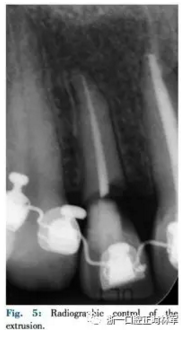

該患者使用舌側全口間接粘接,部分牽引12,使用0.016TMA銅鎳鈦絲(圖3,4,5)。開始階段實現(xiàn)緩慢牽引使12頰側齦緣更接近切端,隨后采用纖維環(huán)切術進行快速牽引以暴露損害邊緣(圖6)。